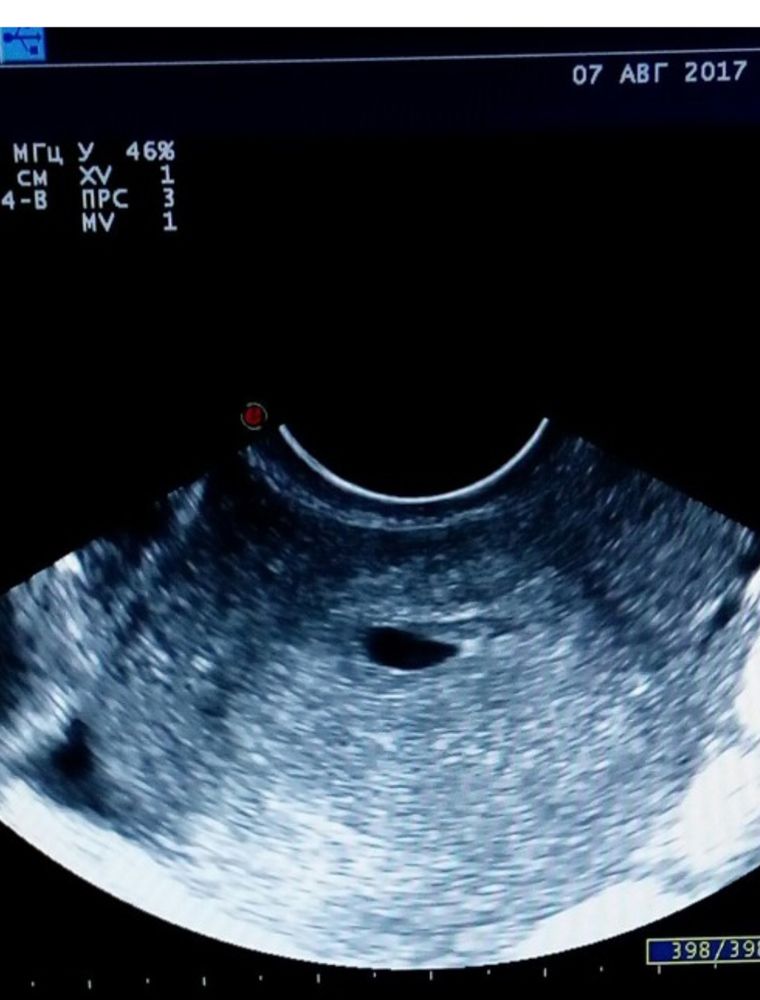

Моя первая дочь была такая, уже с детства чудила, ставили сильный тонус и угрозу, мне лично ничего не говорили, просто написали в заключении, в итоге никаких проблем не было Изображение А вот вторая, отличница)) Изображение

Валентина, у меня вообще как фасолинка была и даже тонус не поставили, вообще никаких проблем не было в первом триместре. Второе конечно идеально круглое👍